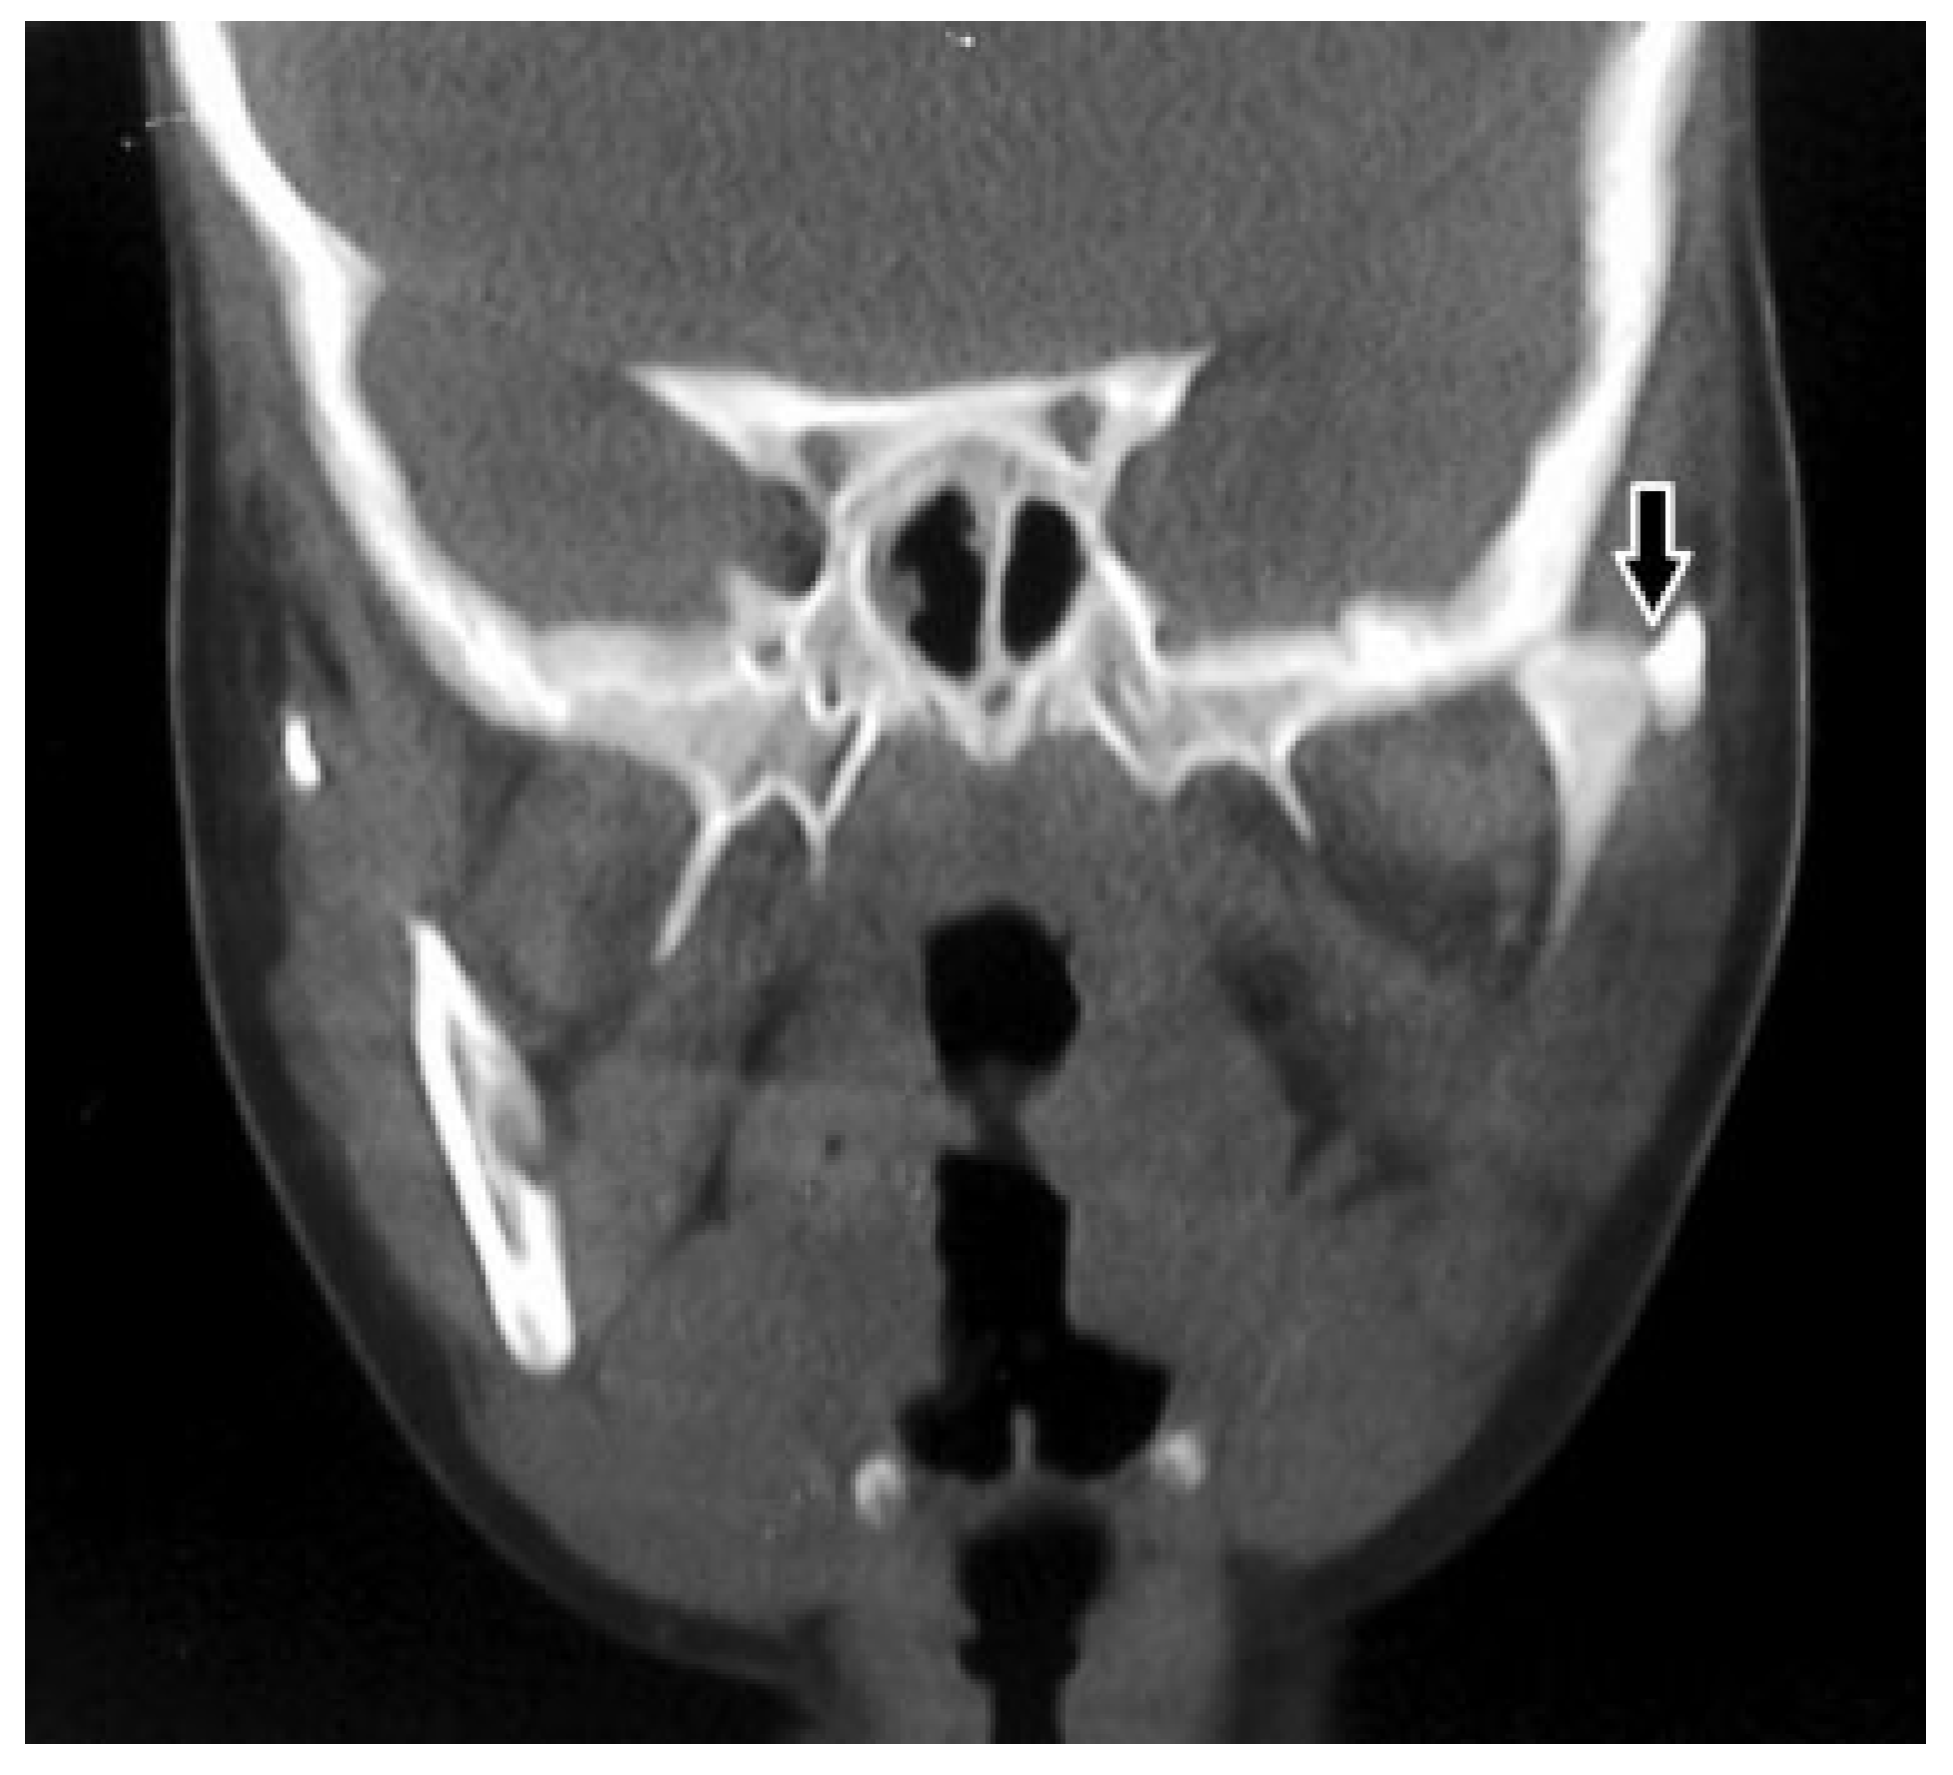

Unusual Superolateral Dislocation of Mandibular Condyle

Case Report